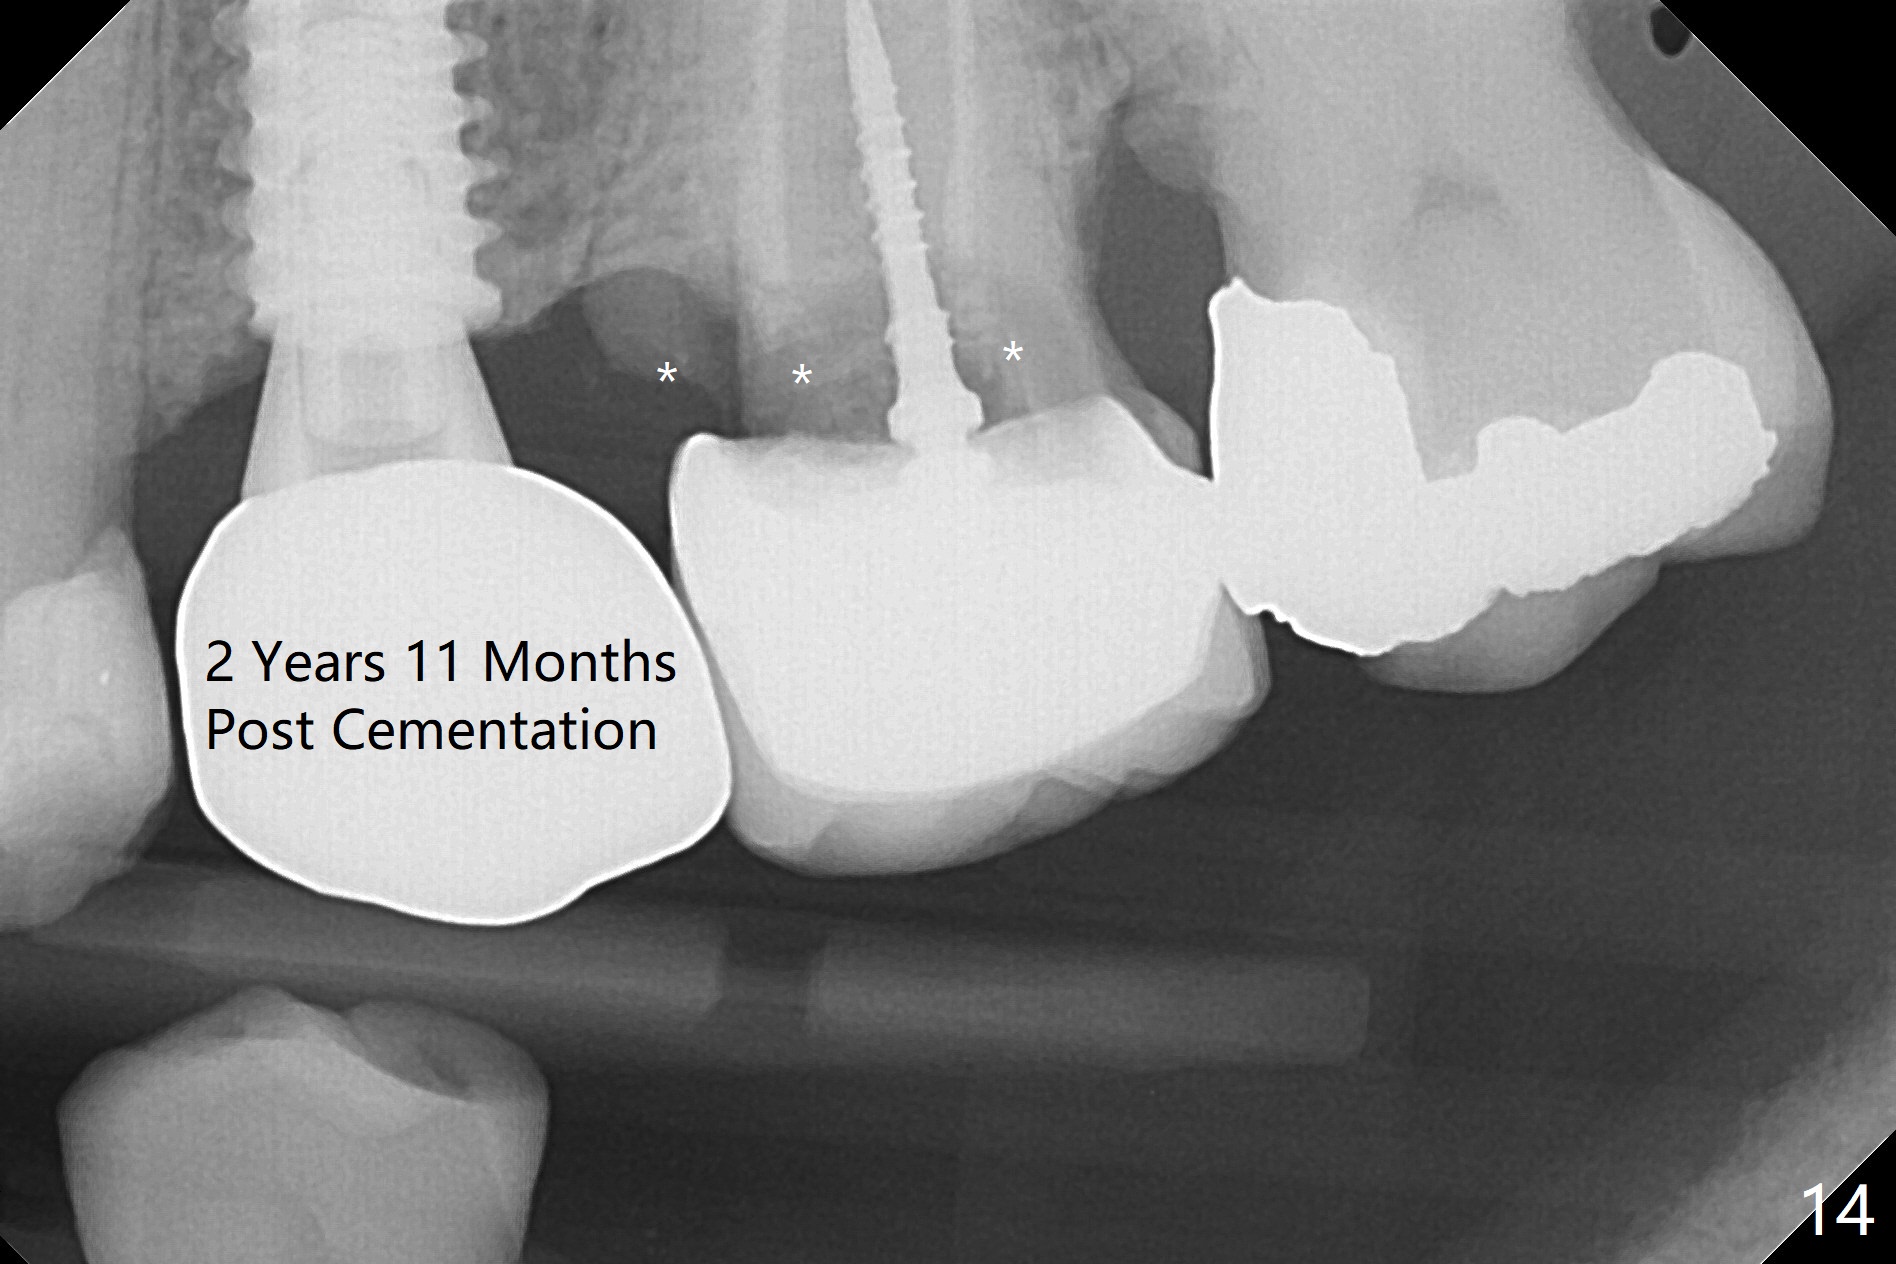

Since the apical native bone is limited at #13 after extraction, no PA is taken until a 4x11 mm dummy implant is placed after 1.6 mm and 3.3 mm drills for 13 mm (Fig.1). After using Lindamann bur to move the osteotomy distal and reusing 3.3 mm drill, the trajectory of a 4.5x11 mm IBS dummy implant improves (Fig.2,3 with low stability). When the implant is removed, the buccal portion of the socket is found to be perforated (Fig.4 P). Although the reason for the perforation is unknown, it is repaired by insertion of a piece of PRF plug, followed by allograft. #1 and 2 in Fig.4 represent the 1st and 2nd osteotomies, as shown in Fig.1 and 2, respectively. The trajectory of the final 5x13 mm implant is acceptable (Fig.5-7, different angulations), so is insertion torque (45 Ncm). After placing a 5.5x4(4) mm abutment, an immediate provisional is fabricated (Fig.8 P) with occlusal clearance (*). The interdental papillae remain in place 12 days postop (Fig.9 *). There is no sign of postop sinus infection. The provisional is loose 18 days postop; the abutment is changed to 5x4(3) mm (Fig.10). It is difficult to catch the mesial margin of the abutment for impression 4 months postop, due to poor oral hygiene and the short cuff (3 mm, Fig.11). The appointment for impression is rescheduled with emphasis on oral hygiene and no wearing the provisional for a few days prior to next appointment. Bone has grown into the space between the 1st and 2nd threads 5 months post cementation (Fig.12) and the bone is normal, solid and dense 2 years 11 months post cementation (Fig.13 >). There is mesial open margin of the tooth #14 (Fig.13,14 *).